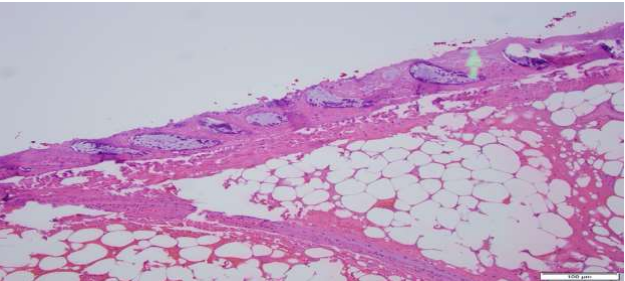

Figure E showing mature lipocytes, acute inflammation and partial fat necrosis as well as overlying colonic mucosa with ulceration as shown by the arrows. Magnification x 40.

An 81-year-old man with history of coronary artery disease on Plavix presented with a large mass protruding from his anus. The patient was straining during defecation and felt severe abdominal and rectal pain. Vital signs and labs were normal. Physical examination revealed left lower quadrant tenderness, and a large mass protruding through his anus. Computed tomography (CT) scan of the abdomen and pelvis revealed a prolapsed 7x5cm sigmoid lipoma with coloanal intussusception, without evidence of obstruction, perforation, or peritonitis (figure A). Attempts to reduce the lipoma manually at bedside were unsuccessful, therefore the patient was taken for emergent resection. The gastrointestinal team was asked to assist so that direct visualization could be used to resect the lipoma stalk. A pediatric colonoscope was inserted alongside the lipoma into the rectum revealing a large stalk of prolapsed colon extending to 20cm from the anal verge (figure B). The retroflexion view showed the stalk traversing the anus surrounded by large hemorrhoids (figure C). The colonoscope could not be advanced past the stalk due to intussusception from the lipoma stalk pulling the colon forwards. Endoloops and a LigaSure device were used to transect the lipoma since the patient was on Plavix and had a high bleeding risk. Using the colonoscope for constant visualization, two Endoloops were placed manually to 10cm from the anal verge using caution to avoid anchoring onto the colonic wall. A third Endoloop was placed at the junction of the lipoma and its stalk at the anal verge. The colonoscope was removed and an Impact LigaSure device was used to slowly transect across the apex of the lesion right at the anal verge with manual pressure to retract the skin, perianal region, rectal mucosa, and hemorrhoids from the LigaSure device (figure D). The colonoscope was then reinserted and the colon was easily traversed up to 40 cm from the anal verge. The stalk was noted to have the two Endoloops in place without bleeding. Pathology revealed a submucosal lipoma with acute inflammation and partial fat necrosis as well as overlying colonic mucosa with ulceration (figure E).

The gold standard for diagnosis is histopathology. Microscopically, lipomas appear as adipose tissue covered by a fibrous capsule, and the overlying mucosa may have ulceration, granulation, or fat necrosis 4,6,7. In our case, the diagnosis was made with CT scan and confirmed by histology.